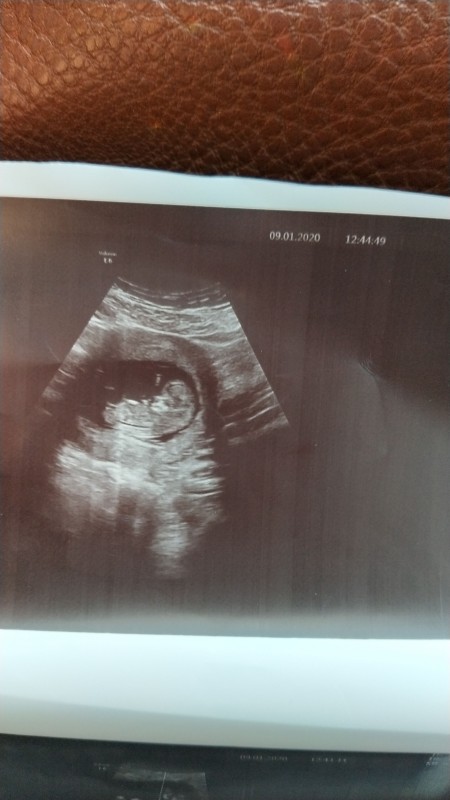

Kizlar ozele gidince ultrasyonda bebek net bir sekilde gozukuyor ama devlette ultrasyona girince bebek tam belli olmuyor iki farkli devlette girdim ikiside net vermedi bebegin durusundan mi kaynakli cihazdan mi?

image

Gebelik haftası 12

Yazıcının kartuşu bitmiş gibi :D

Yaa hic birsey belli degil elime kagidi alinca sasirdim bunun neyini verdi diye

Evet haklısın utrason kalitesiz

Usg cihazı kötü canım bebeğin duruşuyla bir ilgisi yok

Ben de devlete gidiyorum ve gayet net çıkıyor benim. bakın fotoya

Evet ben ozelde bi kac kez cektirdim boyle netti demekki cihazlarinda sorun var ekranda bile net durmuyordu sizin fotografinzdaki kadar

11 ama hic birsey belli degil

Benım devletteki görüntusu cok net

Bu cihaz 80lerden kalma ilk cıkanlardan herhalde